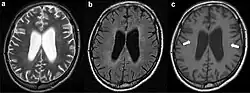

- Leuco-encéphalopathies (Leucoencéphalopathie multifocale progressive)

- Leucoaraiose, forme dégénérative, d'origine vasculaire.

- CADASIL, maladie génétique.